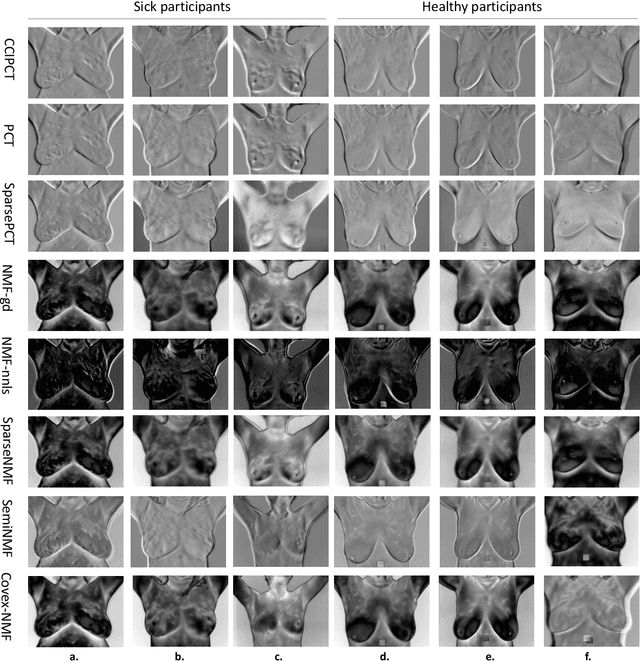

Abstract:Active and passive thermography are two efficient techniques extensively used to measure heterogeneous thermal patterns leading to subsurface defects for diagnostic evaluations. This study conducts a comparative analysis on low-rank matrix approximation methods in thermography with applications of semi-, convex-, and sparse- non-negative matrix factorization (NMF) methods for detecting subsurface thermal patterns. These methods inherit the advantages of principal component thermography (PCT) and sparse PCT, whereas tackle negative bases in sparse PCT with non-negative constraints, and exhibit clustering property in processing data. The practicality and efficiency of these methods are demonstrated by the experimental results for subsurface defect detection in three specimens (for different depth and size defects) and preserving thermal heterogeneity for distinguishing breast abnormality in breast cancer screening dataset (accuracy of 74.1%, 75.8%, and 77.8%).